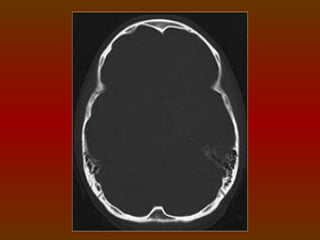

TC CRÂNIO AXIAL

COM JANELA ÓSSEA